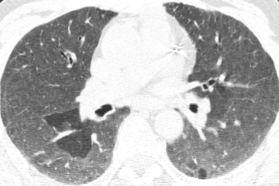

这位慢性纤维化型过敏性肺炎患者就可以看到三种密度征、磨玻璃影、网格影、牵拉性支气管扩张,没有蜂窝。

三种密度征(Three density pattern)里的三个区域分别是:高密度区提示磨玻璃影子,低密度区提示小气道疾病所累及的肺脏出现了气体陷闭的表现,还有一些正常的肺脏。

当出现三种密度征的时候,结合临床,能够高度提示这个患者是 HP。